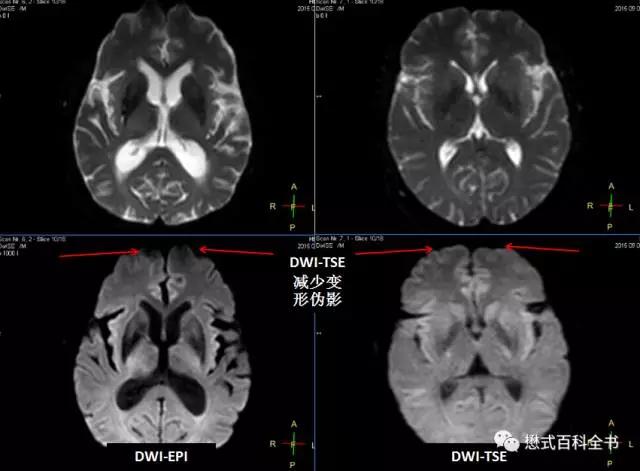

飞利浦公司创新的DWI-TSE序列是一个突破性的改进。我们知道DWI序列一般是采用EPI采集的,结合了EPI采集。而飞利浦可以使用TSE(快速自旋回波)序列做成DWI序列。

TSE序列,由于有多个180°脉冲重聚,所以图像变形小,对磁敏感伪影不敏感。

图18:传统的DWI-EPI弥散序列 vs 飞利浦创新的DWI-TSE弥散序列

由于采用了TSE读出,所以图像变形非常小,而且对磁化率伪影不敏感。

这样的最大优势是用在磁化率敏感区,比如:桥小脑三角区,颈部等部位。

传统上,由于这些部位含有大量气体,导致磁敏感加剧,普通弥散序列变形大,伪影大,根本无法满足临床诊断;而使用飞利浦的DWI-TSE则可以轻松搞定这些部位。

图19-21:DWI-TSE序列减少弥散图像变形,消除磁敏感伪影,对桥小脑三角区和颈部弥散有非常实用的临床意义